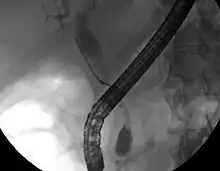

Imaging of the biliary tree

ERCP image of cholangiocarcinoma, showing common bile duct stricture and dilation of the proximal common bile duct

While abdominal imaging can be useful in the diagnosis of cholangiocarcinoma, direct imaging of the bile ducts is often necessary. Endoscopic retrograde cholangiopancreatography (ERCP), an endoscopic procedure performed by a gastroenterologist or specially trained surgeon, has been widely used for this purpose. Although ERCP is an invasive procedure with attendant risks, its advantages include the ability to obtain biopsies and to place stents or perform other interventions to relieve biliary obstruction.[12] Endoscopic ultrasound can also be performed at the time of ERCP and may increase the accuracy of the biopsy and yield information on lymph node invasion and operability.[55] As an alternative to ERCP, percutaneous transhepatic cholangiography (PTC) may be utilized. Magnetic resonance cholangiopancreatography (MRCP) is a non-invasive alternative to ERCP.[56][57][58] Some authors have suggested that MRCP should supplant ERCP in the diagnosis of biliary cancers, as it may more accurately define the tumor and avoids the risks of ERCP.[59][60][61]